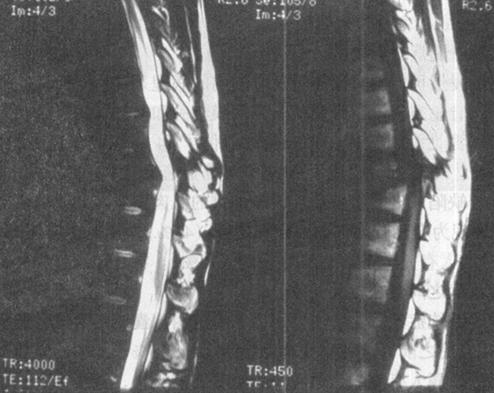

图7-12a 颈段脊髓横断性损伤。颈椎正侧位片:C5以上前脱位,该水平段椎管狭窄,可推测脊髓受压迫

图7-12b MRI矢状面T1WI可见颈髓在C5水平明显受压,椎体前缘和椎管内可见中等偏高信号,局部颈髓可见斑点状高信号;12WI被压迫的脊髓亦见高信号出血灶,脊椎前方前纵韧带下血肿,呈高信号